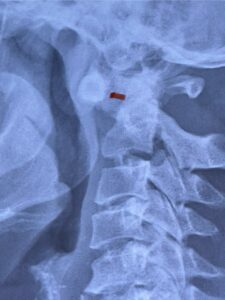

Cervical x-rays revealed a significantly increased atlanto-axial interval (Fig. 5) On review of her imaging studies it was noted that the right C2 isthmus was very thinned by the vertebral foramen (Figs 6a, b, and c) which would make an attempt at placing a C2 pars screw dangerous. A decision was made to perform an occipital-cervical fusion because only possible unilateral fixation and an extensive C1 laminectomy to be performed eliminating a fixation point if a more traditional C1-C2 was performed. Even if C1 lateral mass screws were able to be placed one could only perform a unilateral screw construct fixation to C2. We performed an occipital cervical fusion down to C4 to get enough inferior fixation and C1 laminectomy. The decompression went well. We placed a left unilateral pars screw and bilateral C3 and C4 lateral mass screws. We placed three 12 mm screws in the midline keel (Fig. 7). Postoperatively the patient had all around improvement in her symptoms and did not qualify for rehab. Her post op films at 6 weeks (Fig. 8)

Fig. 5: Lateral cervical x-ray demonstrating widened atlanto-dens interval as a result of instability (red dash).